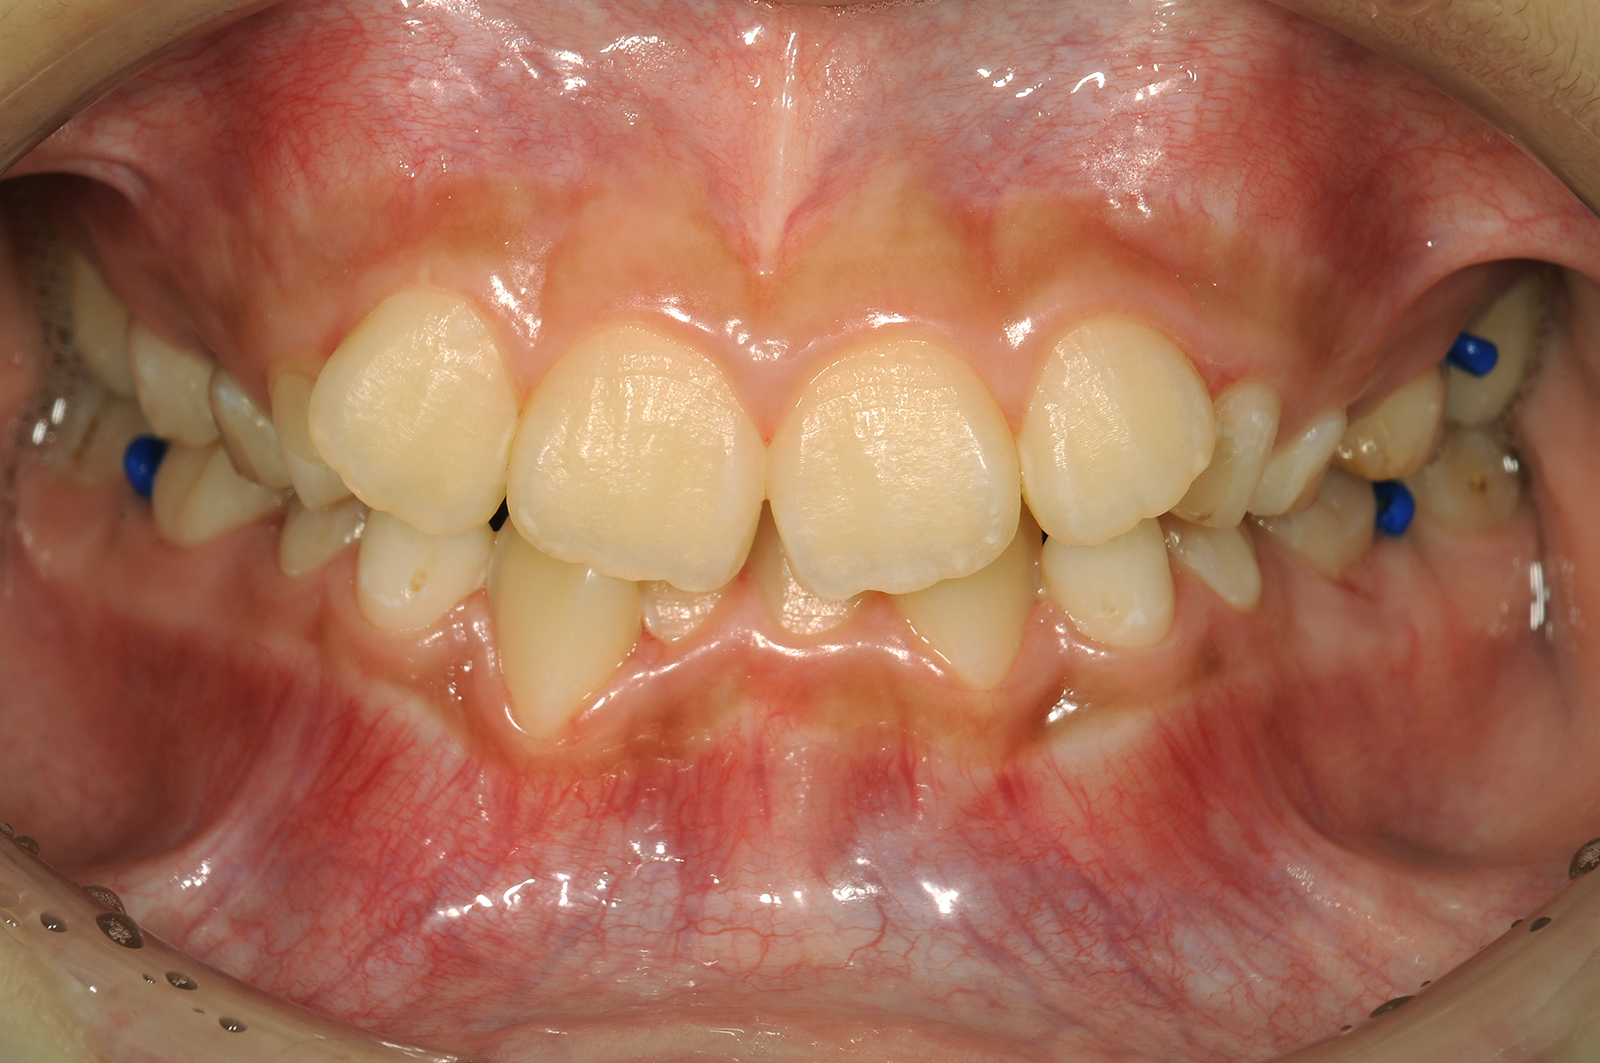

顎の小ささと大きな歯の組み合わせは、歯が適切に配置されるスペースが不足することを意味します。その結果、歯が重なり合い、不規則に生えてしまうことがあります。

ご説明した通り、歯並びが悪くなる原因の1つは小さな顎で歯が生えるスペースが不足していることです。

子どもの成長過程でこの顎の問題を矯正し、歯が適切に並ぶスペースを確保することで、歯並びの根本的な原因に対処することが可能です。